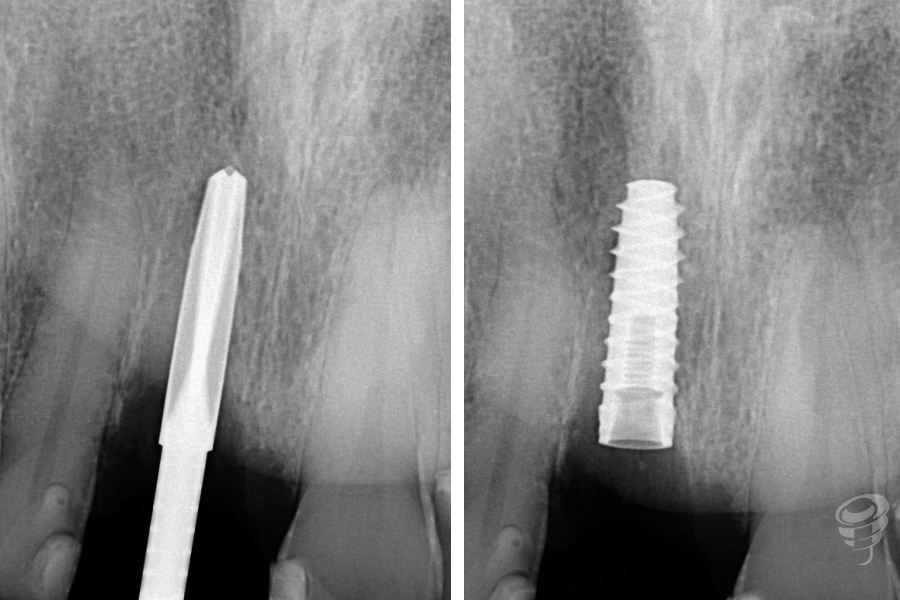

- Preparación del lecho implantario: Secuencia quirúrgica con fresas bajo irrigación abundante.

Figura 8

- Colocación del implante: Implante cónico de titanio grado IV (IPX 4012) con torque de inserción de 40 Ncm. Posición: 3mm apical al CEN del diente adyacente, 2mm palatino a la tabla vestibular.

Figura 9